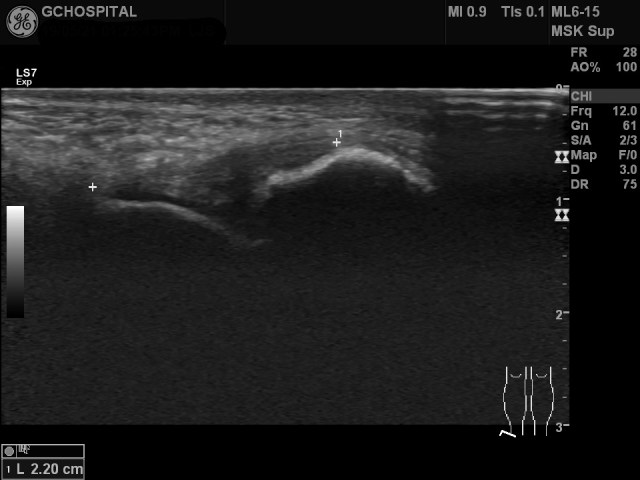

실제로 anterior talofibular ligament가 발목을 어떻게 구부리는가에 따라 길이가 변하는지 초음파영상에서도 확인할 수 있습니다. 인대를 더 길게 늘인 상태에서 관찰해야 인대 자체의 확인도 쉽고, 인대의 손상여부도 민감하게 확인할 수 있습니다.

Anterior talofibular ligament는 위와 같이 platarflexion한 상태에서 훨씬 더 잘 관찰할 수 있는 반면, calcaneofibular ligament는 반대로 dorsiflexion 시 더 길어지고, 잘 보입니다.